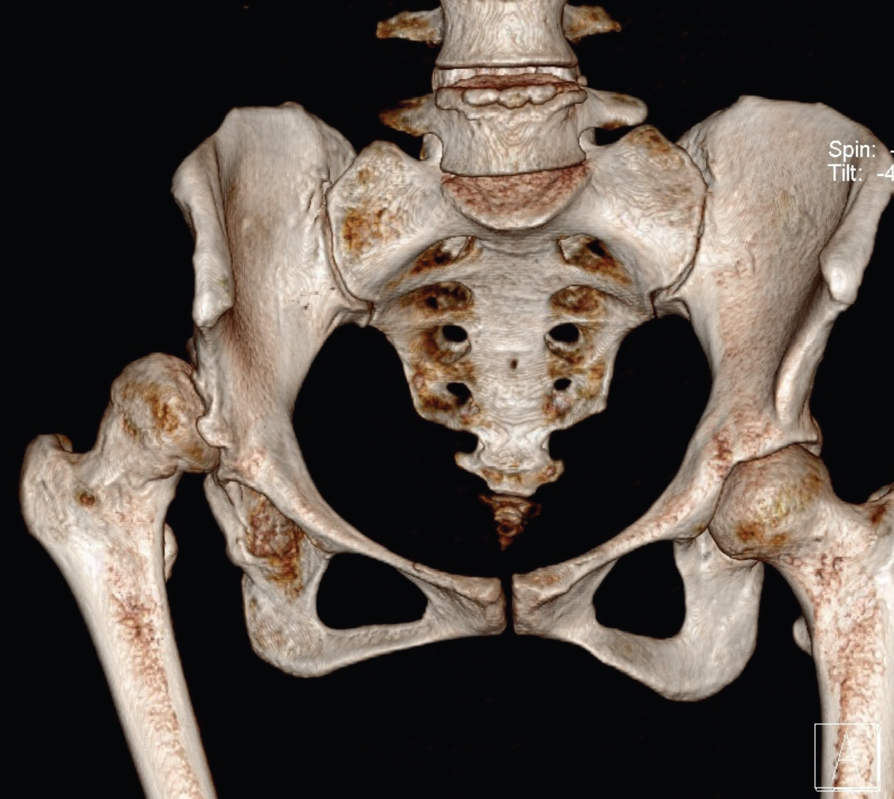

Gelişimsel kalça displazisine bağlı artrozun üç boyutlu BT’si